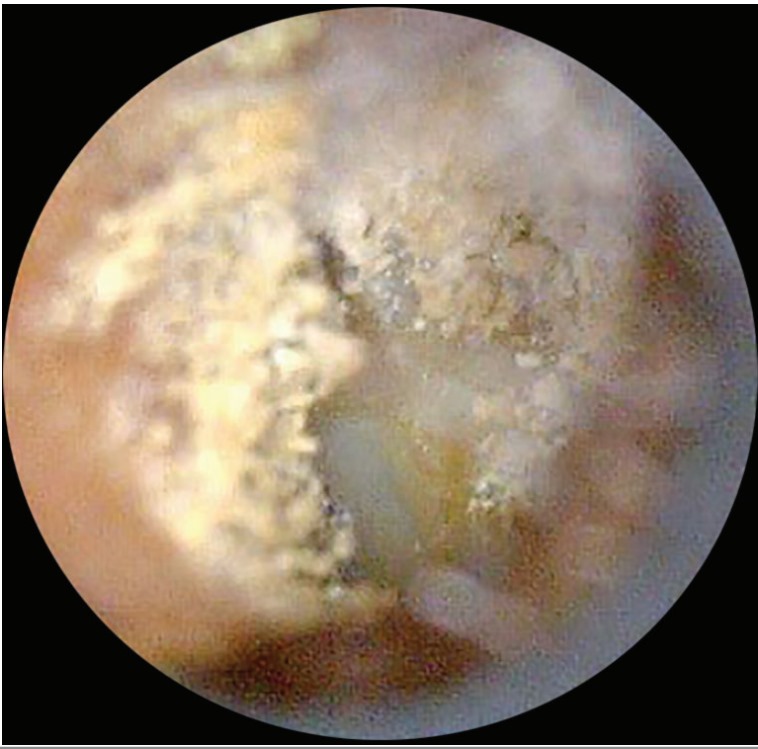

- Otorhinolaryngology